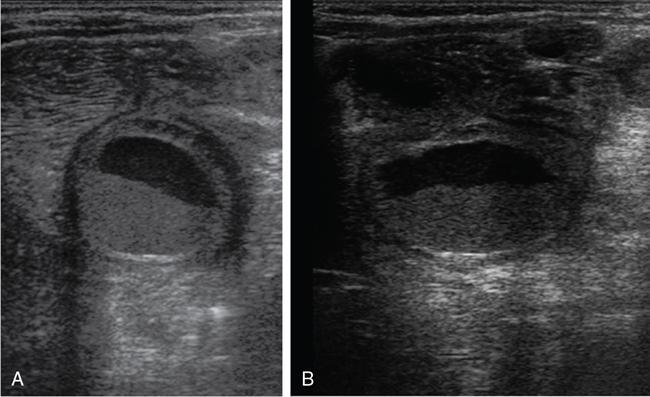

Rashmi Dixit, Anju Garg Abdominal masses are a common clinical problem in children, arising from virtually any abdominal organ. Masses arising from the gastrointestinal (GI) tract are not uncommon. They may be congenital or developmental, inflammatory, infective, idiopathic or neoplastic in nature. A high index of suspicion is necessary so as to ensure an early diagnosis and appropriate management. Imaging, therefore, plays a vital role in identifying the location, nature and extent of the mass lesion. Ultrasound (US) is the first-line imaging method for GI masses, like for most paediatric abdominal masses. It does not require sedation and is nonionizing which are important considerations in the paediatric population. US findings may be diagnostic in certain masses when no further imaging is required. Computed tomography (CT) plays an important role in complete evaluation of GI masses especially where US is either not diagnostic or the full extent and nature of the mass needs to be delineated, especially prior to surgery. It requires the administration of intravenous contrast and preferably oral contrast as well. Sedation may be required and it carries the risk of radiation exposure. Each study, hence, needs to be tailored to answer the clinical question at hand, while ensuring the lowest possible radiation exposure. Magnetic resonance imaging (MRI) provides excellent contrast resolution, which along with its nonionizing nature makes it a very attractive imaging technique. However, due to the relatively long imaging time requiring sedation, sensitivity to motion both respiratory and bowel and limited availability it is generally used as a problem-solving tool. Plain films and contrast studies currently have a very limited role in the evaluation of GI masses. Plain films may be diagnostic in masses like teratomas, while contrast studies may be required for mucosal abnormalities and small endoluminal masses like polyps. Enteric duplication cysts can occur along any portion of the GI tract from the pharynx to the rectum. They are found most often in the ileum (33%). The other sites are the oesophagus (20%), colon (13%), jejunum (10%), stomach (7%) and duodenum (5%). The incidence is reported to be around 0.2% of all children, with a slight male predominance. Duplication cysts are thought to arise between the 4th and 8th weeks of development; however, their aetiology is unknown and several different theories have been proposed. In 16%–26% cases there may be associated spinal defects, cardiac or urinary malformations. Other associated GI anomalies may be seen in about 10% of cases. Duplication cysts typically lie along the mesenteric border of the gut. They have smooth muscle wall which they share with the adjacent gut, as also the blood supply. On histopathology, three classical features are seen: an epithelial lining with GI mucosa, a smooth muscle covering and a close attachment to the GI tract due to a shared common wall. Although the mucosal lining does not necessarily match with the adjacent portion of the gut, nonetheless, duplications are named after the portion of the gut to which these are closely related. About 20%–30% of these duplication cysts contain ectopic gastric mucosa which is more common in oesophageal and small intestinal duplication cysts. Ectopic pancreatic mucosa may also be seen, most often in gastric duplication cysts. Morphologically they may be cystic or tubular with the former accounting for 80% and the latter for 20%. While cystic duplications mostly do not communicate with the adjacent gut, tubular duplications that run parallel to the GIT often do, hence in these cases connection with GIT must be demonstrated for operative planning. Duplication cysts may be multiple in 1%–7% of cases usually occurring in the same segment of the GIT. An atypical duplication cyst is an isolated duplication cyst which is completely separated from the GIT and has no communication or shared wall with the gut. They are extremely rare and thought to be the result of a vascular injury. Although duplication cysts may remain asymptomatic till adulthood they mostly present within the first year (70%). Almost 85% present by the second year. Clinical features depend not only on the size and location, but also on the presence of any ectopic mucosa and complications. Pharyngeal and oesophageal cysts may present with respiratory distress or dysphagia. Infection and rapid growth may cause retrosternal pain or haemoptysis. Gastric and intestinal duplications cause nonspecific symptoms like recurrent abdominal pain nausea, vomiting, distention or a palpable lump. High pressure inside the cyst consequent to accumulation of secretions is thought to be responsible for the recurrent abdominal pain. Obstruction due to intussusception or extrinsic compression may occur. Presence of gastric mucosa is associated with complications like inflammation, bleeding, ulceration and perforation. US is most useful for the diagnosis of abdominal duplication cysts and sometimes may demonstrate these on an antenatal scan. MR and CT are mainly used for oesophageal duplication and for planning surgery. Endoscopic trans oesophageal ultrasound may be informative for oesophageal duplications but is not a part of routine practice. Classical US features in uncomplicated duplication cysts include: a unilocular cystic structure in close proximity to the bowel. The cyst has a relatively thick wall which has a hyperechoic inner lining representing the mucosa and an outer hypoechoic rim produced by the smooth muscle layer (muscularis propria) – the so-called ‘gut signature’ sign. This sign is also referred to as the ‘double-wall’ or ‘muscular rim’ sign. (Fig. 7.7.1) Though, most characteristically described for duplication cysts, it may sometimes be seen in some other cystic lesions such as a complicated mesenteric cyst, Meckel’s diverticulum or torsed ovarian cyst. Some US signs described recently are: the ‘five layered cyst wall sign’ and ‘Y configuration of the muscle wall sign’. It has been shown that with the use of high frequency US transducers (12–18 MHz) the wall of the duplication cyst can demonstrate the same five layered wall structure as the normal GIT. From inside to outside these are: the innermost mucosa which is hyperechoic, muscularis mucosa (hypoechoic), hyperechoic submucosa, hypoechoic muscularis propria and the outermost serosa which is hyperechoic. If all these five layers can be identified in a cyst it is diagnostic of an enteric duplication cyst; however, the sign is difficult to demonstrate (Fig. 7.7.2A and B). The second sign arises because a duplication cyst shares its wall with the adjacent gut. Splitting of the common muscularis propria between the cyst and the adjoining bowel loop results in the Y configuration of the muscle layer on US, reflecting one of its important histological features. When this is seen, it is possible to confidently diagnose an enteric duplication cyst as this sign has not been demonstrated in other cysts. The ‘Y configuration sign’ can be particularly valuable in complicated cysts In addition, since US is a real time examination it also allows visualization of peristalsis of the cyst wall which is seen as a transient change in the cyst shape and contour due to contraction of the cyst wall (Fig. 7.7.3A and B). This requires the transducer to be kept stationary over the cyst for some time Most duplication cysts are anechoic but some echoes due to mucinous fluid or septations can be seen at times, and do not imply complications. Complications include haemorrhage (due to ectopic gastric mucosa), enzymatic destruction of the mucosal lining, inflammation (due to ectopic pancreatic tissue) and infection. In these cases, fluid levels or echogenic debris can be seen within the cyst with a thick hypervascular wall which may lack layers (see Fig. 7.7.2B). In these cases, the Y configuration sign can help to suggest the correct diagnosis. The inflammatory changes may extend to the surrounding mesenteric fat as well, which becomes hyperechoic. Duplication cysts near the ileocecal valve, can act as a lead point for intussusception. Atypical or isolated duplication cysts, may just produce the pseudokidney sign. The important US features of duplication cysts are listed in Box 7.7.1. Key Ultrasound Signs of Duplication Cysts CT is not performed for the diagnosis of duplication cysts, however, it can demonstrate the location, anatomical relationships, exact extent and the associated anomalies. On CT evaluation a cystic mass closely related to the adjoining GI wall is seen. The wall shows mild enhancement. A complicated duplication cyst showing internal high attenuation, air foci, thick enhancing wall and surrounding inflammation suggests infection (Fig. 7.7.4A and B). Internal high attenuation alone, however, could be due to proteinaceous contents or haemorrhage and does not imply infection on its own. MR is also not generally used as a diagnostic tool due to long examination times requiring sedation but is especially useful to demonstrate the cystic nature of thoracic duplications. Duplications cysts show hypointense signal on T1W sequences and very high signal on T2W images. Both CT and MR may be used prior to surgery. MR may have an additional value in assessment of foetal abdominal cysts. Differential diagnosis includes other cystic lesions such as mesenteric, omental, ovarian and choledochal cysts. In patients with an antenatal diagnosis, although the optimal time for resection is not defined, it is suggested that early resection within the first 6 months be considered. Treatment of asymptomatic duplication cysts remains controversial, however, since early elective surgery is associated with less morbidity and a shorter hospital stay than excision in symptomatic cases, it should be preferred. In addition, complications such as obstruction or massive bleeding may be life threatening and there is a potential risk for malignant transformation in adults. The cyst can be removed alone, but if there is a communication with the adjoining gut its resection will be required. Currently, minimally invasive surgery is becoming the procedure of choice. Complete excision is important to avoid cyst recurrence or subsequent malignant changes. Hypertrophic pyloric stenosis was earlier believed to be a developmental anomaly but is currently thought to be acquired disorder. It is characterized by hypertrophy of the circular muscle layer of the pylorus. This results in thickening and lengthening of the pylorus ultimately progressing to gastric outlet obstruction. The etiopathogenesis of this disorder is unknown but postulated mechanisms include abnormal innervation of the pylorus and duodenal irritation due to hypersecretion. Various genetic and environmental factors such as maternal smoking and use of erythromycin have also been implicated. Several ultrastructural anomalies have been identified in the muscle layer including abnormal nerve endings, decreased synthesis of nitric oxide, reduction in the number of cells of Cajal and an increased production of insulin-like growth factors. These factors are thought to cause muscle hypertrophy and failure of muscle relaxation. The incidence of HPS is about 3 per 1000 live births with male to female ratio of 4–5:1. Patients usually present between 2 and 6 weeks of age. The child is typically normal at birth and, subsequently develops non-bilious vomiting around 2–3 weeks of age. There may be a small lump palpable in the epigastrium, the so called ‘pyloric olive’, in nearly 80% of cases. Also, peristalsis may be seen traversing the epigastrium. If vomiting persists, dehydration and hypochloraemic alkalosis can develop. In the presence of a classical history and examination findings, the diagnosis is often made clinically and imaging is only used to confirm the diagnosis. US allows visualization of the pyloric canal morphology as well as behaviour during dynamic evaluation. Ultrasonography is performed with a high-frequency transducer ranging between 6 and 15 MHz. The child is placed supine and the examination is best performed with a moderately fluid-filled stomach. The first step is to localize the gallbladder as the pylorus lies posteromedial to the gallbladder. Another useful trick is to first localize the upper pole of the right kidney and then move the transducer medially towards the xiphoid to identify the pylorus. The transducer is then angulated so that the pyloric canal is well visualized in long axis. Correct positioning so that the pyloric canal is seen as a straight line is important to ensure that measurements are not performed in a tangential plane which can result in fallacious increase in muscle thickness. Sometimes a gas distended stomach may preclude visualization of the pylorus. In this case, shifting the child to an oblique position so that the right side is placed inferiorly allows fluid to move into the antrum which acts as an acoustic window. A markedly distended stomach can displace the pylorus posteriorly making it difficult to visualize. In this situation moving the child so that the left side is down or prone positioning may help localize the pylorus. Distention of the stomach with water rather than milk may be a better option as milk may at times also cause artefacts. A nasogastric tube may be used to fill up the stomach when necessary. The most important diagnostic feature of HPS is thickening of the muscle layer of the pylorus seen as hypoechoic curved bundles between the antrum and duodenal cap. A number of signs that have been described on sonography in HPS include the ‘empty cervix’ sign as the hypertrophied muscle mass indents the fluid filled antrum and duodenal bulb mimicking the appearance of cervix in longitudinal section (Fig. 7.7.5). The hypertrophied pylorus gives appearance of a ‘doughnut or a target’ in transverse section. The ‘antral nipple’ or ‘mucosal nipple sign’ refers to redundant pyloric canal mucosa protruding into the antrum. This can be seen as an echogenic structure protruding into the fluid filled antrum (Fig. 7.7.6). The fluid trapped between the mucosal folds in the centre of an elongated pylorus may be seen as two sonolucent lines in the centre referred to as the ‘double track sign’. Measurement of muscle layer thickness provides objective assessment of pyloric thickening. A muscle layer thickness of more than 3 mm is considered abnormal. This should be measured from the outer echogenic edge of the mucosa to the outer edge of the muscle on both transverse and longitudinal scans. A muscle wall thickness of less than 2 mm is considered normal while a thickness between 2 and 3 mm is considered equivocal as it can be seen in other conditions like pylorospasm or gastritis besides HPS. Pyloric canal length of less than 14 mm is thought to be unequivocally normal. A pyloric canal length of more than 15–17 mm is also considered diagnostic for HPS (Fig. 7.7.6). However, the measurement of canal length is much more difficult to perform and subject to variability, hence this should not be used alone to make the diagnosis of HPS. Total diameter of the pylorus over 13 mm and pyloric volume measurements have also been suggested, but muscle thickness measurement remains the most accurate In addition, real-time observation of the pyloric behaviour is also important. The stomach tends to be markedly distended and shows increased peristalsis with failure of gastric contents to pass into the duodenum. The other hand a wide-open pylorus with normal passage of contents into the duodenum excludes the diagnosis of HPS (Box 7.7.2). Key Ultrasound Features of Hypertrophic Pyloric Stenosis There is a higher incidence of renal anomalies in these patients and hence kidneys should be examined once diagnosis is established. Pitfalls in sonographic diagnosis include non-visualization of the pylorus due to an overdistended stomach pushing it posteriorly, tangential views of the pylorus or pylorus spasm producing a pseudo thickening of the pylorus. Hence it is important to make sure that the pylorus is correctly imaged and the entire pyloric length is visualized in longitudinal plane. As opposed to pylorus spasm the thickening and the appearance of pylorus in HPS tends to persist, while pylorospasm is transient and generally resolves within 30 minutes. If the muscle layer measures 2–3 mm in thickness and the pylorus does not relax during the US examination clinical follow up and repeat US examination may be advisable. Borderline measurements are more likely to occur in preterm infants. Some authors have provided measurements of the pyloric length and muscle thickness correlated with the age and weight of the child which may be helpful in small and premature patients. In equivocal cases, it is preferable to perform a repeat examination rather than erroneously make a false-positive diagnosis, as HPS is not a surgical emergency. A barium study may be performed if the US examination is inconclusive. Use of a nasogastric tube is preferred as it allows a controlled filling of the stomach with barium. The upper GI barium study shows delayed emptying of the stomach. The pyloric canal is elongated and narrowed visualized as a curved streak of barium directed upwards and posteriorly, referred to as the ‘string sign’. This combination of narrowed pyloric canal along with elongation is the most important feature of HPS on contrast studies. A ‘double string sign’ is produced when barium is caught between the folds of mucosa overlying the hypertrophied muscle. ‘Antral beaking’ refers to a mass impression upon the antrum with a streak of barium entering the narrowed pyloric canal. The hypertrophied muscle may indent the gastric antrum as well as the duodenal bulb producing the ‘shoulder sign’. Disruption of the antral peristalsis may result in a small outpouching along the lesser curvature of stomach producing the ‘pyloric teat’ sign. The stomach shows hyperperistalsis on fluoroscopic examination which is sometimes referred to as the ‘caterpillar sign’ (Box 7.7.3). These signs may sometimes be seen in pylorospasm but are not persistent. Therefore, it is important that the study is of sufficient duration to establish the persistence of findings. Any the residual barium must be aspirated if a nasogastric tube has been placed, in order to avoid aspiration. Key Upper GI Features of Hypertrophic Pyloric Stenosis The treatment of HPS is surgical, that is, Ramstedt’s pyloromyotomy. Postoperatively, in the first week, the muscles may remain same in thickness or even thicker than that prior to surgery. The muscle thickness gradually returns to normal with the anterior part of the muscle normalising first followed by the posterior portion. The anterior portion usually returns to a thickness of 3 mm within 3 months whereas the posterior portion may take up to 5 months to normalize. This is related to the usual anterior surgical approach. The gastric emptying, however, returns to normal within 2–3 days. An upper GI examination may also be used to assess gastric emptying postoperatively and to exclude gastro-oesophageal reflux if vomiting persists. GI polyps are commonly seen in childhood between 2 and 5 years of age and are the most common cause of painless rectal bleeding in children. Juvenile polyps are the most common type of polyps that are seen in children accounting for about 80% of the polyps. The term juvenile refers to the histology of the polyp rather than the age at which they occur. Histologically these lesions represent benign hamartomas. Diagnosis is made via rectal examination or sigmoidoscopy. Radiological examination is rarely required for diagnosis. Polyps in the distal colon and rectum can be easily resected via endoscopic polypectomy. Inflammatory polyps are commonly seen in children with inflammatory bowel disease. Most of these polyps are actually pseudo polyps formed by hyperplastic and inflamed mucosa in areas of inflammation and mucosal injury. They may reach large sizes but are not pre-malignant. Imaging reveals evidence of inflammatory bowel disease along with polyps. Juvenile polyposis syndrome is an inherited condition characterized by multiple juvenile polyps. The following criteria must be met for diagnosis of JPS (a) more than 5 juvenile polyps in the colon or rectum (b) juvenile polyps in other portions of the GI tract (c) any number of juvenile polyps with a positive family history. Single juvenile polyps are not a feature of juvenile polyposis syndrome. JPS has been categorized into 3 types depending on the clinical features and age of onset. Diffuse juvenile polyposis of infancy presenting in children up to 3 months of age. generalized juvenile polyposis with polyps throughout the GIT and juvenile polyposis coli (JPC) with polyps only in the colon beginning in children and adolescents. Children can present with diarrhoea, rectal bleeding, intussusceptions or anaemia. The diagnosis is usually established by colonoscopy. Double-contrast barium enema or CT colonogram can also demonstrate multiple polyps within the colon. Peutz-Jeghers syndrome is rare autosomal dominant disorder characterized by hamartomatous polyps throughout the GI tract. Mutation of ATK tumour suppressor gene is seen in some cases. Histologically these polyps are characterized by a smooth muscle core arising from the muscularis mucosa. Although polyps occur anywhere in the GI tract, they are commonest in the small bowel. They can be sessile or pedunculated and being firm in nature (due to the smooth muscle core) are particularly prone to intussusception. They may also present as GI bleed and anaemia Although the polyps of PJS are benign hamartomas the syndrome is associated with an increased risk of malignancy (adenocarcinoma). The diagnosis of PJS can be made if there are 2 or more histologically confirmed PJS polyps, any number of PJS polyps along with the typical mucocutaneous pigmentation, a family history of PJS with any number of PJS polyps or the presence of mucocutaneous pigmentation with family history of PJS. Because of the presence of small bowel polyps CT enterography, MR enterography and small bowel enema also have an important role to play in the diagnosis. The polyps are seen as sessile or pedunculated intraluminal filling defects on these studies. They may also be seen as the lead point of an intussusception (Fig. 7.7.7). Endoscopy and colonoscopy are used to establish the diagnosis. Video capsule endoscopy is especially useful to identify the polyp burden in the small bowel. The treatment is aimed at removing the larger polyps either surgically or endoscopically so as to avoid obstruction.